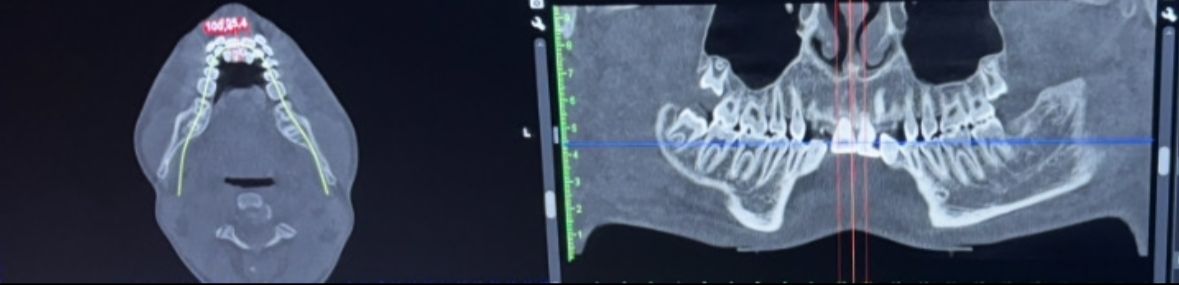

i have this